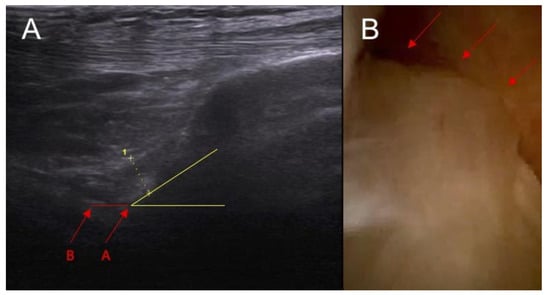

Figure 7.

(A) ACL tear confirmed in arthroscopy view. Swelling of the ACL/PCL compartment with change of the morphology of the posterior joint capsule complex in (marked with red arrows) MRI view (B) and ultrasound view (C).

Dynamic instability was notably more prevalent in patients with ACL injuries (p < 0.0001). Among patients without an ACL injury, 23% exhibited dynamic instability within a range of 3–4 mm. In stark contrast, all patients with ACL injuries showed signs of dynamic instability: 33% of these patients had instability within the 3–4 mm range, while a 67% experienced instability ≥ 5 mm.

The ultrasound test's ability to detect ACL damage based on abnormal ACL inclination has a sensitivity of 67% and a specificity of 92%. When assessing ACL damage through the presence of swelling in the ACL compartment using ultrasound, the test shows 83% sensitivity and 100% specificity. For detecting ACL damage by identifying swelling in the ACL/PCL compartment with ultrasound, the sensitivity is 88% and the specificity reaches 100%. The test’s effectiveness in diagnosing ACL damage through dynamic instability evaluation under ultrasound is 100% sensitive and 77% specific. It is important to note that in cases where patients with 3–4 mm and ≥5 mm abnormalities were categorized as injured, the sensitivity drops to 67% while specificity increases to 100% if only those in the ≥5 mm category are considered to be affected.